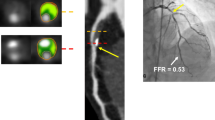

Studies of anatomical imaging, whether it be quantitative coronary angiography, CCTA or intravascular ultrasound, have consistently demonstrated an unreliable relationship between anatomic measures of stenosis and lesion-specific ischemia [15]. The ability to evaluate the functional significance of stenosis using FFR during ICA improves outcomes and reduces health care cost [8••, 9••]. However, considering the invasiveness of ICA, a new non-invasive approach to calculate total vessel FFR based on CCTA has been developed [21]. FFRCT applies computational fluid dynamics (CFD) to calculate FFR values in all epicardial coronary arteries without the need for additional imaging, medications, or change in imaging protocol [22]. FFRCT is based on three steps (Fig. 1): (1) reconstruction of a 3D model that includes the aortic root and coronaries, (2) identification of inflow and outflow boundary conditions that mimic coronary physiology during maximal hyperemia, and (3) performing a numerical solution of the laws governing fluid dynamics [21]. The color-coded 3D model is obtained from a standard CCTA acquisition in accordance with Society of Cardiovascular Computed Tomography guidelines [22].

FFRCT analysis. From a standard CCTA (Panel a), a quantitative 3-dimensional anatomic model of coronary arteries is generated. b A physiological model of the coronary microcirculation is derived from patient-specific characteristics and physical laws of fluid dynamics is applied (c) to calculate FFRCT for each point in the coronary tree (d). CCTA coronary computed tomography angiography, FFRCT: fractional flow reserve CCTA derived, LAD left anterior descending coronary artery, LCx left circumflex coronary artery, RCA right coronary artery. Modified by Pontone et al. [61••].

FFRCT has been extensively validated against invasive FFR (Table 1). In the DeFACTO study, diagnostic accuracy of FFRCT + CCTA was superior to CCTA alone compared with invasive FFR (73 % vs. 64 %, respectively) [23]. In addition, FFRCT demonstrated greater discrimination of lesion-specific ischemia compared to CCTA (area under the curve (AUC) of 0.81 vs 0.68) [23]. Despite the significant improvement in diagnostic accuracy of CCTA when integrated with FFRCT, a partial discrepancy between invasive FFR and FFRCT in the DeFACTO study was observed. This result could be attributed to nitroglycerin and beta-blockers not being mandatory in the protocol translating into a degradation in image quality [24]. In a sub-study of DeFACTO, for individuals with intermediate coronary stenosis, FFRCT had a negative predictive value of 90 %, allowing the clinician to rule-out intermediate lesions that cause ischemia [25]. A limitation of DISCOVER-FLOW was that it was powered to evaluate the diagnostic accuracy in a per-vessel model rather than a per-patient model. The latter point was evaluated in the DE-FACTO trial [26] where, in a larger study population, FFRCT showed a diagnostic accuracy, sensitivity, specificity, positive predictive value, and negative predictive value of 73, 90, 54, 67, and 84 %, respectively, improving the AUC from 0.68 to 0.81 when compared with CCTA alone. More recently, the NXT trial [27••] demonstrated per patient sensitivity and specificity of 86 and 79 %, respectively, with an even better AUC of 0.9 as compared to invasive FFR. In contrast to the two previous studies, in the NXT trial, a new generation of FFRCT software was employed, nitrates were administered in 99 % versus only 75 % of DEFACTO study population, and an intermediate risk population was included rather than patients with a higher risk as in DEFACTO and DISCOVER-FLOW. Importantly, in patients with intermediate stenosis [27••] and in patients with high Agatston score [28] the diagnostic performance of FFRCT remained unchanged. Of note, FFRCT was not-evaluable in 13 % of the NXT-trial patients due to poor image quality [27••].

In a real-world feasibility study, Nørgaard et al. [29] proposed the “Aarhus” algorithm in which patients with FFRCT lower than 0.75 were referred to ICA, patients with FFRCT ranging between 0.75 to 0.80 were followed clinically for symptom evolution and patients with FFRCT > 0.80 were deferred from ICA. In the same study, a conclusive FFRCT result was obtained in 98 % of patients [29]. One of the great advantages of FFRCT is that it does not increase radiation dose as it is quantified from standard CCTA datasets [30]. Several CCTA imaging protocol strategies have been described in the literature to decrease radiation dose while maintaining good image quality. Interestingly, Bilbey et al. [30] calculated the differential radiation dose simulating various common diagnostic pathways based on the first non-invasive diagnostic test performed. The population was divided in four groups: dobutamine echo, SPECT, CCTA, and CCTA+ FFRCT. Radiation dose exposure for CTA + FFRCT was lower than for SPECT, and the CTA + FFRCT pathway resulted in the lowest projected death or myocardial infarction rate at 1 year (2.33 %). Although the radiation dose was lowest in the pathway that used dobutamine echo, the dobutamine stress pathway had the highest 1-year event rate [30].

The ability to identify a specific plaque that causes ischemia utilizing FFRCT is proving to be cost-effective. The PLATFORM trial (Prospective LongitudinAl Trial of FFRCT: Outcome and Resource IMpacts) compared the rate of ICA documenting non-obstructive CAD, clinical outcomes, quality of life, and resource utilization following standard practice versus incorporating FFRCT [31]. The PLATFORM investigators demonstrated that in patients with planned ICA, the approach using FFRCT safely canceled 61 % of ICA, reduced ICAs with no obstructive CAD by a dramatic 83 %, improved quality of life for patients, and reduced healthcare cost [32••, 33]. Finally, exciting data from the EMERALD study was recently presented using CFD-based non-invasive hemodynamics for the prediction of acute coronary syndromes. Culprit lesions had significantly lower FFRCT and higher delta FFRCT (across lesions), axial plaque and wall shear stress compared to non-culprit lesions. The ability of these non-invasive hemodynamic parameters to better identify culprit lesions causing acute coronary syndrome as compared to anatomic stenosis severity or high risk plaque features could help fill the ambitious gap to diagnose the vulnerable lesion and patient.